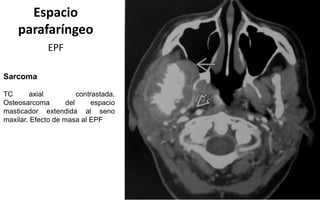

Sarcoma

TC axial contrastada.

Osteosarcoma del espacio

masticador extendida al seno

maxilar. Efecto de masa al EPF